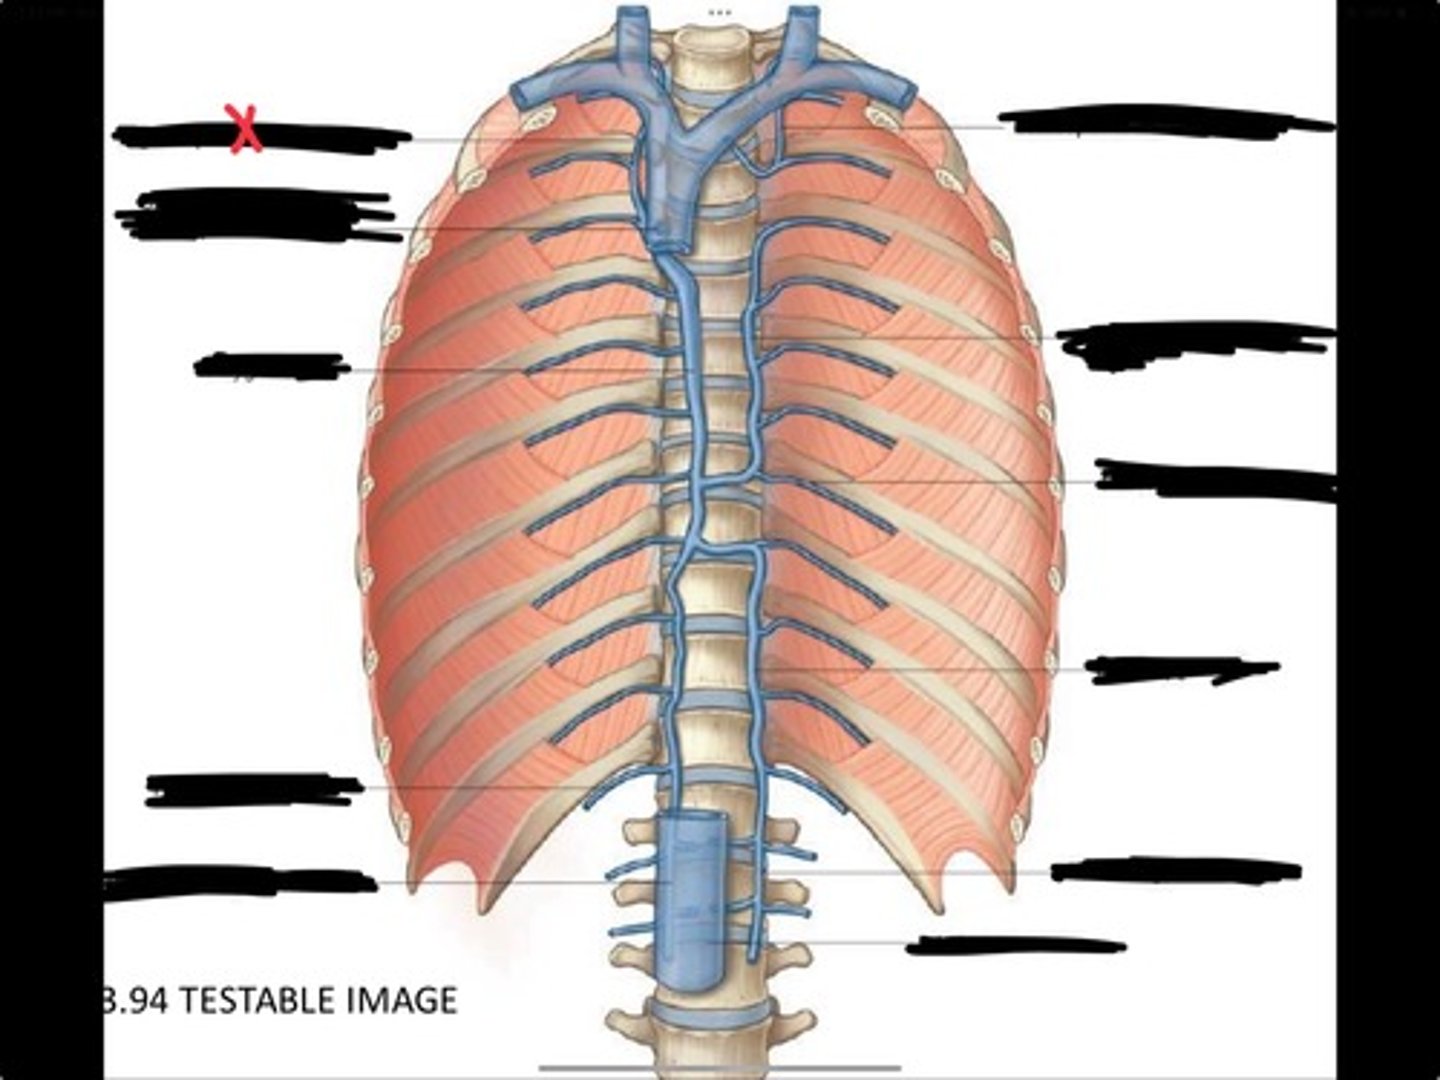

Right ascending lumbar vein

Right subcostal vein

Azygos vein

Opening of the azygos vein into superior vena cava

Right superior intercostal vein

Left superior intercostal vein

Accessory hemiazygos vein

Posterior intercostal vein

Hemiazygous vein

Ascending lumbar vein